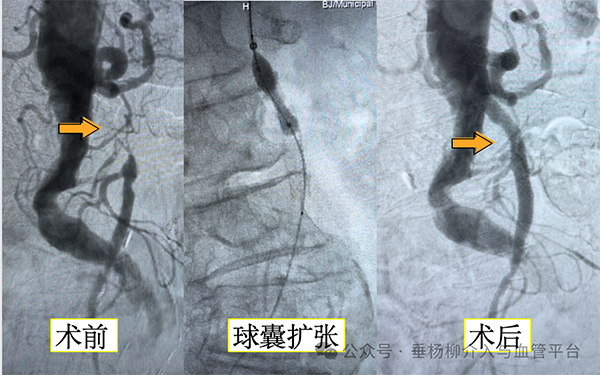

“这是缺血性肠病!”满新贺一下就发现了病人的主要病因。满大夫才把这一发现告诉了陈阿姨和她的家人,最终家人同意进行血管介入开通手术。在杨永久主任指导下,手术进行得很顺利,满医生和郑医生用球囊把狭窄的血管撑开,还放进了支架,让供应小肠的血液重新顺畅地流动起来。